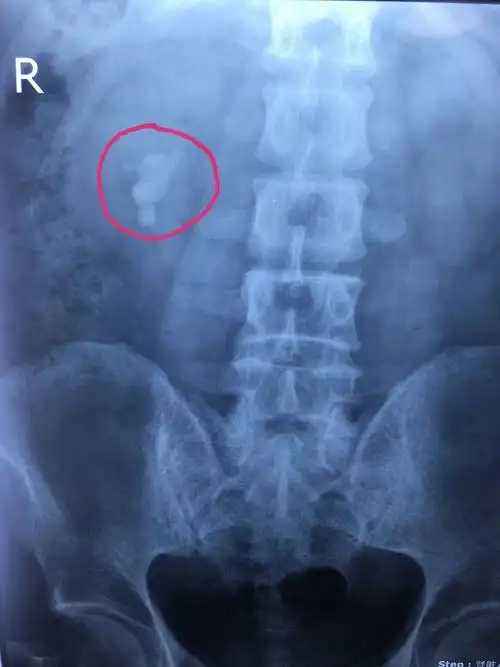

图16 左肾结石

ct影像显示巨大肾结石(红圈内)